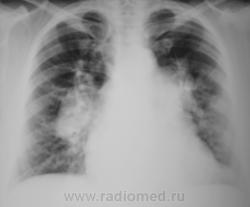

Какие мнения будут по выставленным изображениям.

Предположительно - саркоидоз.

Сначало надо решить: за счет чего такие корни. Лимфоузлы? А может оказаться и митральным стенозом с гипертензией в МККО.

На данной томограмме по правому контуру четко видна дуга увеличенного левого предсердия. Стрелки указывают на артериальные сосуды 3 сегмента. При лимфоаденопатии мы бы не увидели трахеобронхиальный угол и непарную вену справа. Стало быть: Cor mitrale с активной артериальной гипертензией МКК.

Вероятно у пациента перегородочный врожденный порок сердца с артериальной гипертензией и последующим дистрофическим поражением и снижением тонуса миокарда.

Что-то я не врублюсь. Почему гипертрофировано  левое предсердие по малому радиусу? Разве при септальных пороках оно страдает?

Как это так это? Вторая дуга по правому контуру сердца возникает только от увеличенного левого предсердия. Пусть будет ДМПП, митральный порок, кардиомиопатия, кардиомидистрофия с расширением всех камер сердца. Давйте попросим контрастировать пищевод.

Конечно это дуга левого предсердия, но оценивать и ориентироваться  нужно на его толщину, а не поперечник. Конечно здесь все камеры увеличены, так как имеет место диффузное снижение тонуса миокарда, но относительно других камер увеличение небольшое, и имеет место дилятация, небольшая...

У меня получилось: увеличен левый желудочек (может и дилятирован) и левое предсердие (надуто, как мяч, скорее всего гипертрофировано, кривизна явно малого радиуса). Может не так померял?

Конечно, логика подсказывает, что если это гипертрофированное левое предсердие (а оно може быть таким только при митральном стенозе), тогда откуда такой дилятированный левый желудочек (а он как раз при таком пороке работает в полухолостую). А если это не левое предсердие, тогда что?

вообщем пришли к выводу, что саркоидоза нету, да?

А его и не было (саркоидоза). Пациентка давно находится на учете по поводу врожденного порока сердца, просто, случай показался интересным, вот, я, и решил его выставить.